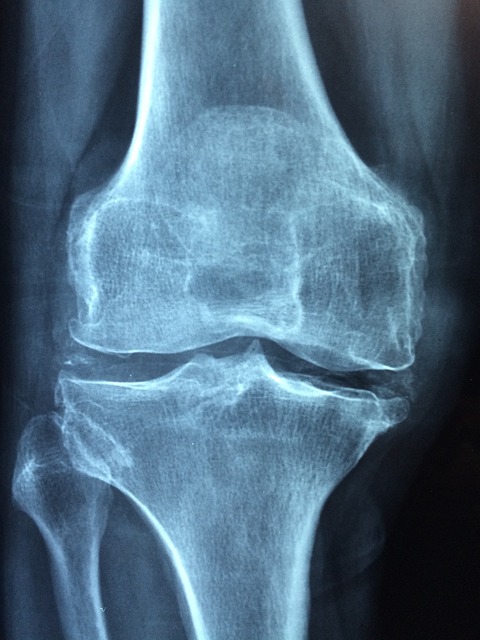

물 차는 증상 분석

정상적인 무릎에는 약 2~3ml의 활액이 존재합니다.

염증이 생기면 이 양이 20~50ml까지 증가하면서 무릎이 팽팽해집니다.

무릎 위쪽을 누르면 물렁물렁한 느낌이 들고, 슬개골을 눌렀을 때 뼈가 가라앉는 느낌이 납니다.

이런 증상을 슬개골 부유 검사 양성이라고 하며 관절 삼출의 확실한 증거입니다.

물이 차는 원인은 과사용, 외상, 연골 손상, 관절염 등 다양합니다.

러너들의 경우 반복적인 충격으로 인한 미세 외상이 가장 흔한 원인입니다.